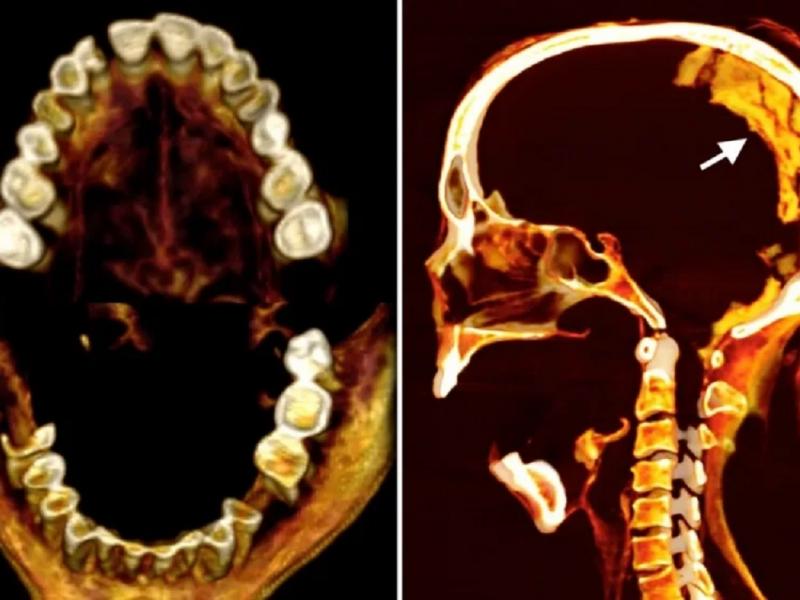

Εξακολουθώντας να γοητεύεται από την «γυναίκα που ουρλιάζει» που πέθανε πριν από περίπου 3.500 χρόνια, μια διαφορετική ομάδα επιστημόνων χρησιμοποίησε πρόσφατα αξονικές τομογραφίες για να αποκαλύψει λεπτομέρειες σχετικά με τη μορφολογία, τις συνθήκες υγείας και τη συντήρηση της μούμιας και χρησιμοποίησε υπέρυθρες απεικονίσεις και άλλες προηγμένες τεχνικές για να «τεμαχίσει εικονικά» τα λείψανα και να κατανοήσει τι μπορεί να προκάλεσε την εντυπωσιακή έκφραση του προσώπου της.

Τα ευρήματά τους, που δημοσιεύθηκαν την Παρασκευή στο περιοδικό Frontiers in Medicine, αποκάλυψαν ότι η γυναίκα ήταν 48 ετών όταν πέθανε, με βάση την ανάλυση μιας άρθρωσης που βρίσκεται στη λεκάνη, η οποία αλλάζει με την ηλικία. Ορισμένες πτυχές της διαδικασίας που χρησιμοποιήθηκαν για τη μουμιοποίησή της, ξεχώρισαν.

Οι ερευνητές διαπίστωσαν ότι η ανώνυμη γυναίκα είχε ύψος 1,54 μέτρα, δηλαδή λίγο πάνω από 1,5 μέτρο, και έπασχε από ήπια αρθρίτιδα της σπονδυλικής στήλης, με τις τομογραφίες να αποκαλύπτουν οστικές εκβλαστήσεις σε ορισμένους σπονδύλους που αποτελούν τη σπονδυλική στήλη. Από το σαγόνι της γυναίκας έλειπαν επίσης αρκετά δόντια, τα οποία πιθανότατα είχαν χαθεί πριν από το θάνατο.